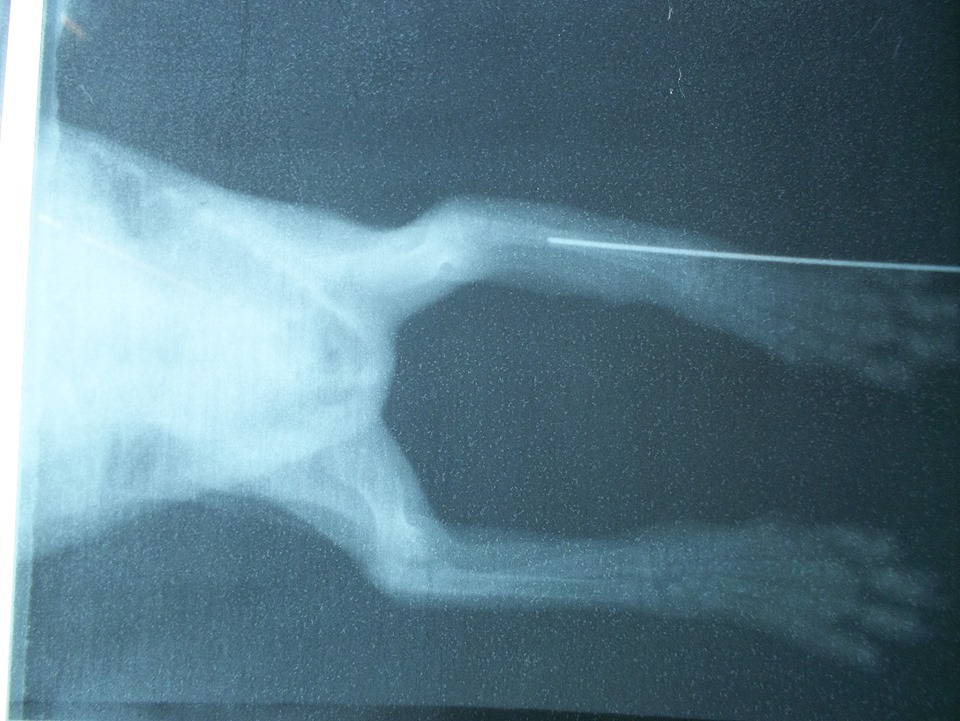

主題: 右前腳被捕獸夾夾斷之小黑貓 申請者姓名: 許桂菱 花色: 申請日期: 2013-12-11 00:29:38 申請者部落格: 申請者臉書網址: 所在縣市/合作醫院: 彰化縣/成愛動物醫院 治療費用: 6200元 需求人數: 8人 已結案 (2014-01-10 17:49:01) 報名人員: tiffany、劉定惠、Justin Wang(已付款)、Tiffany Shen(已付款)、小月(已付款)、shirina(已付款)、徐芳芳(已付款)、Chen-Pang Chang、Captainken Lai(已付款)、詩詩(已付款)、潼潼(已付款)、 候補人員: 牛豬魚、 動物病情說明: 鹿港貓友於下班時聽到小貓哀叫聲,尋找叫聲發現其公司後門旁的私人雜物間有隻小黑貓被捕獸夾夾傷,故緊急向志工求救,志工無法立即趕至現場,請貓友先抓至合作之動物醫院緊急處理,經照X光後右前腳夾扁,醫生施作打釘接連固定,因傷了神經前腳掌沒有反應且無法正翻,小貓目前也只有兩個月大,需持續觀察未來是否需要截肢!

狂犬疫苗費用由志工負擔動物近況說明: 由發現的貓友帶回照料,已尋求中醫針灸但醫生認為沒有幫助,故需等待小黑貓再大一點觀察扁骨連接生長情況才能再評估!